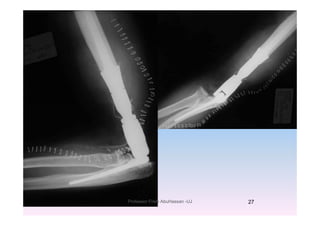

E t i l i th j i tExtensive lesions near the joint

Total elbow arthroplastyTotal elbow arthroplasty

1/14/2011 26Professor Freih AbuHassan -UJ

1/14/2011 27Professor Freih AbuHassan -UJ

F M tForearm Mets

Plate fixation with PMMA